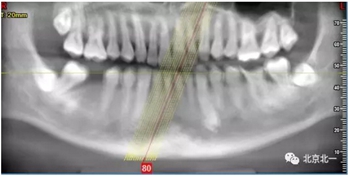

檢查:46缺失, 47傾斜, 1度松動(dòng), 未見48萌出,

CBCT:骨量高度及寬度可, 48埋伏,低位阻生.37近中骨吸收

診斷:下頜牙列缺損, 48低位埋伏阻生 37 牙周炎

治療計(jì)劃:46種植, 同期拔除48 正畸扶正47.